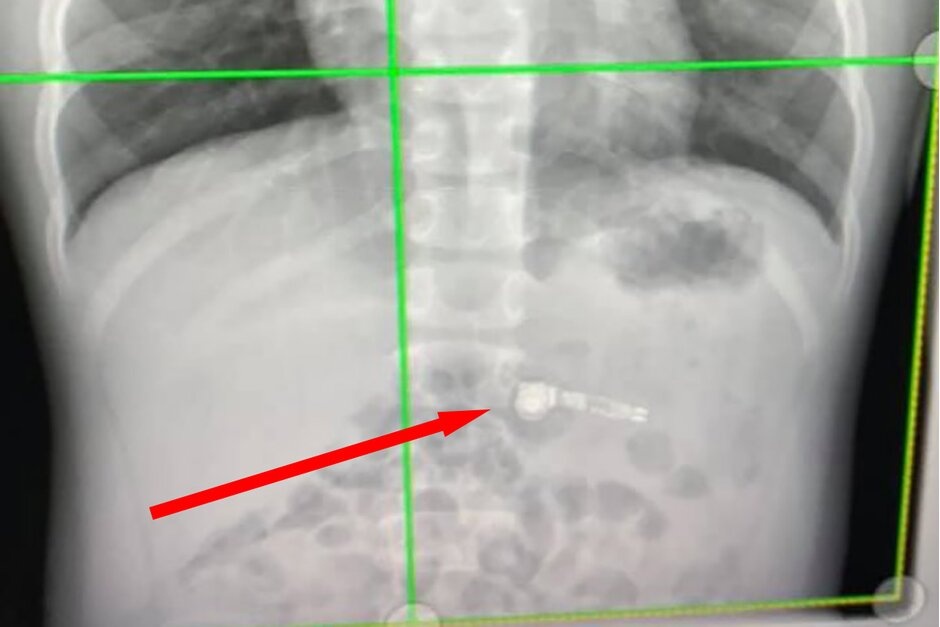

Các bác sĩ cũng tỏ ra ngạc nhiên khi phát hiện chiếc AirPods bên trong bụng của cậu bé. Ảnh: PhoneArena.

Tại bệnh viện chăm sóc sức khỏe trẻ em Atlanta Egelston, các bác sĩ đã sử dụng phương pháp chụp x-quang ổ bụng và xác định được vị trí của chiếc AirPods.

"Một chiếc AirPods? Nó thật kỳ lạ. Tôi chưa từng gặp điều gì tương tự trước đây", các bác sĩ tại bệnh viện tỏ ra ngạc nhiên khi người mẹ nói về tình trạng của cậu bé.